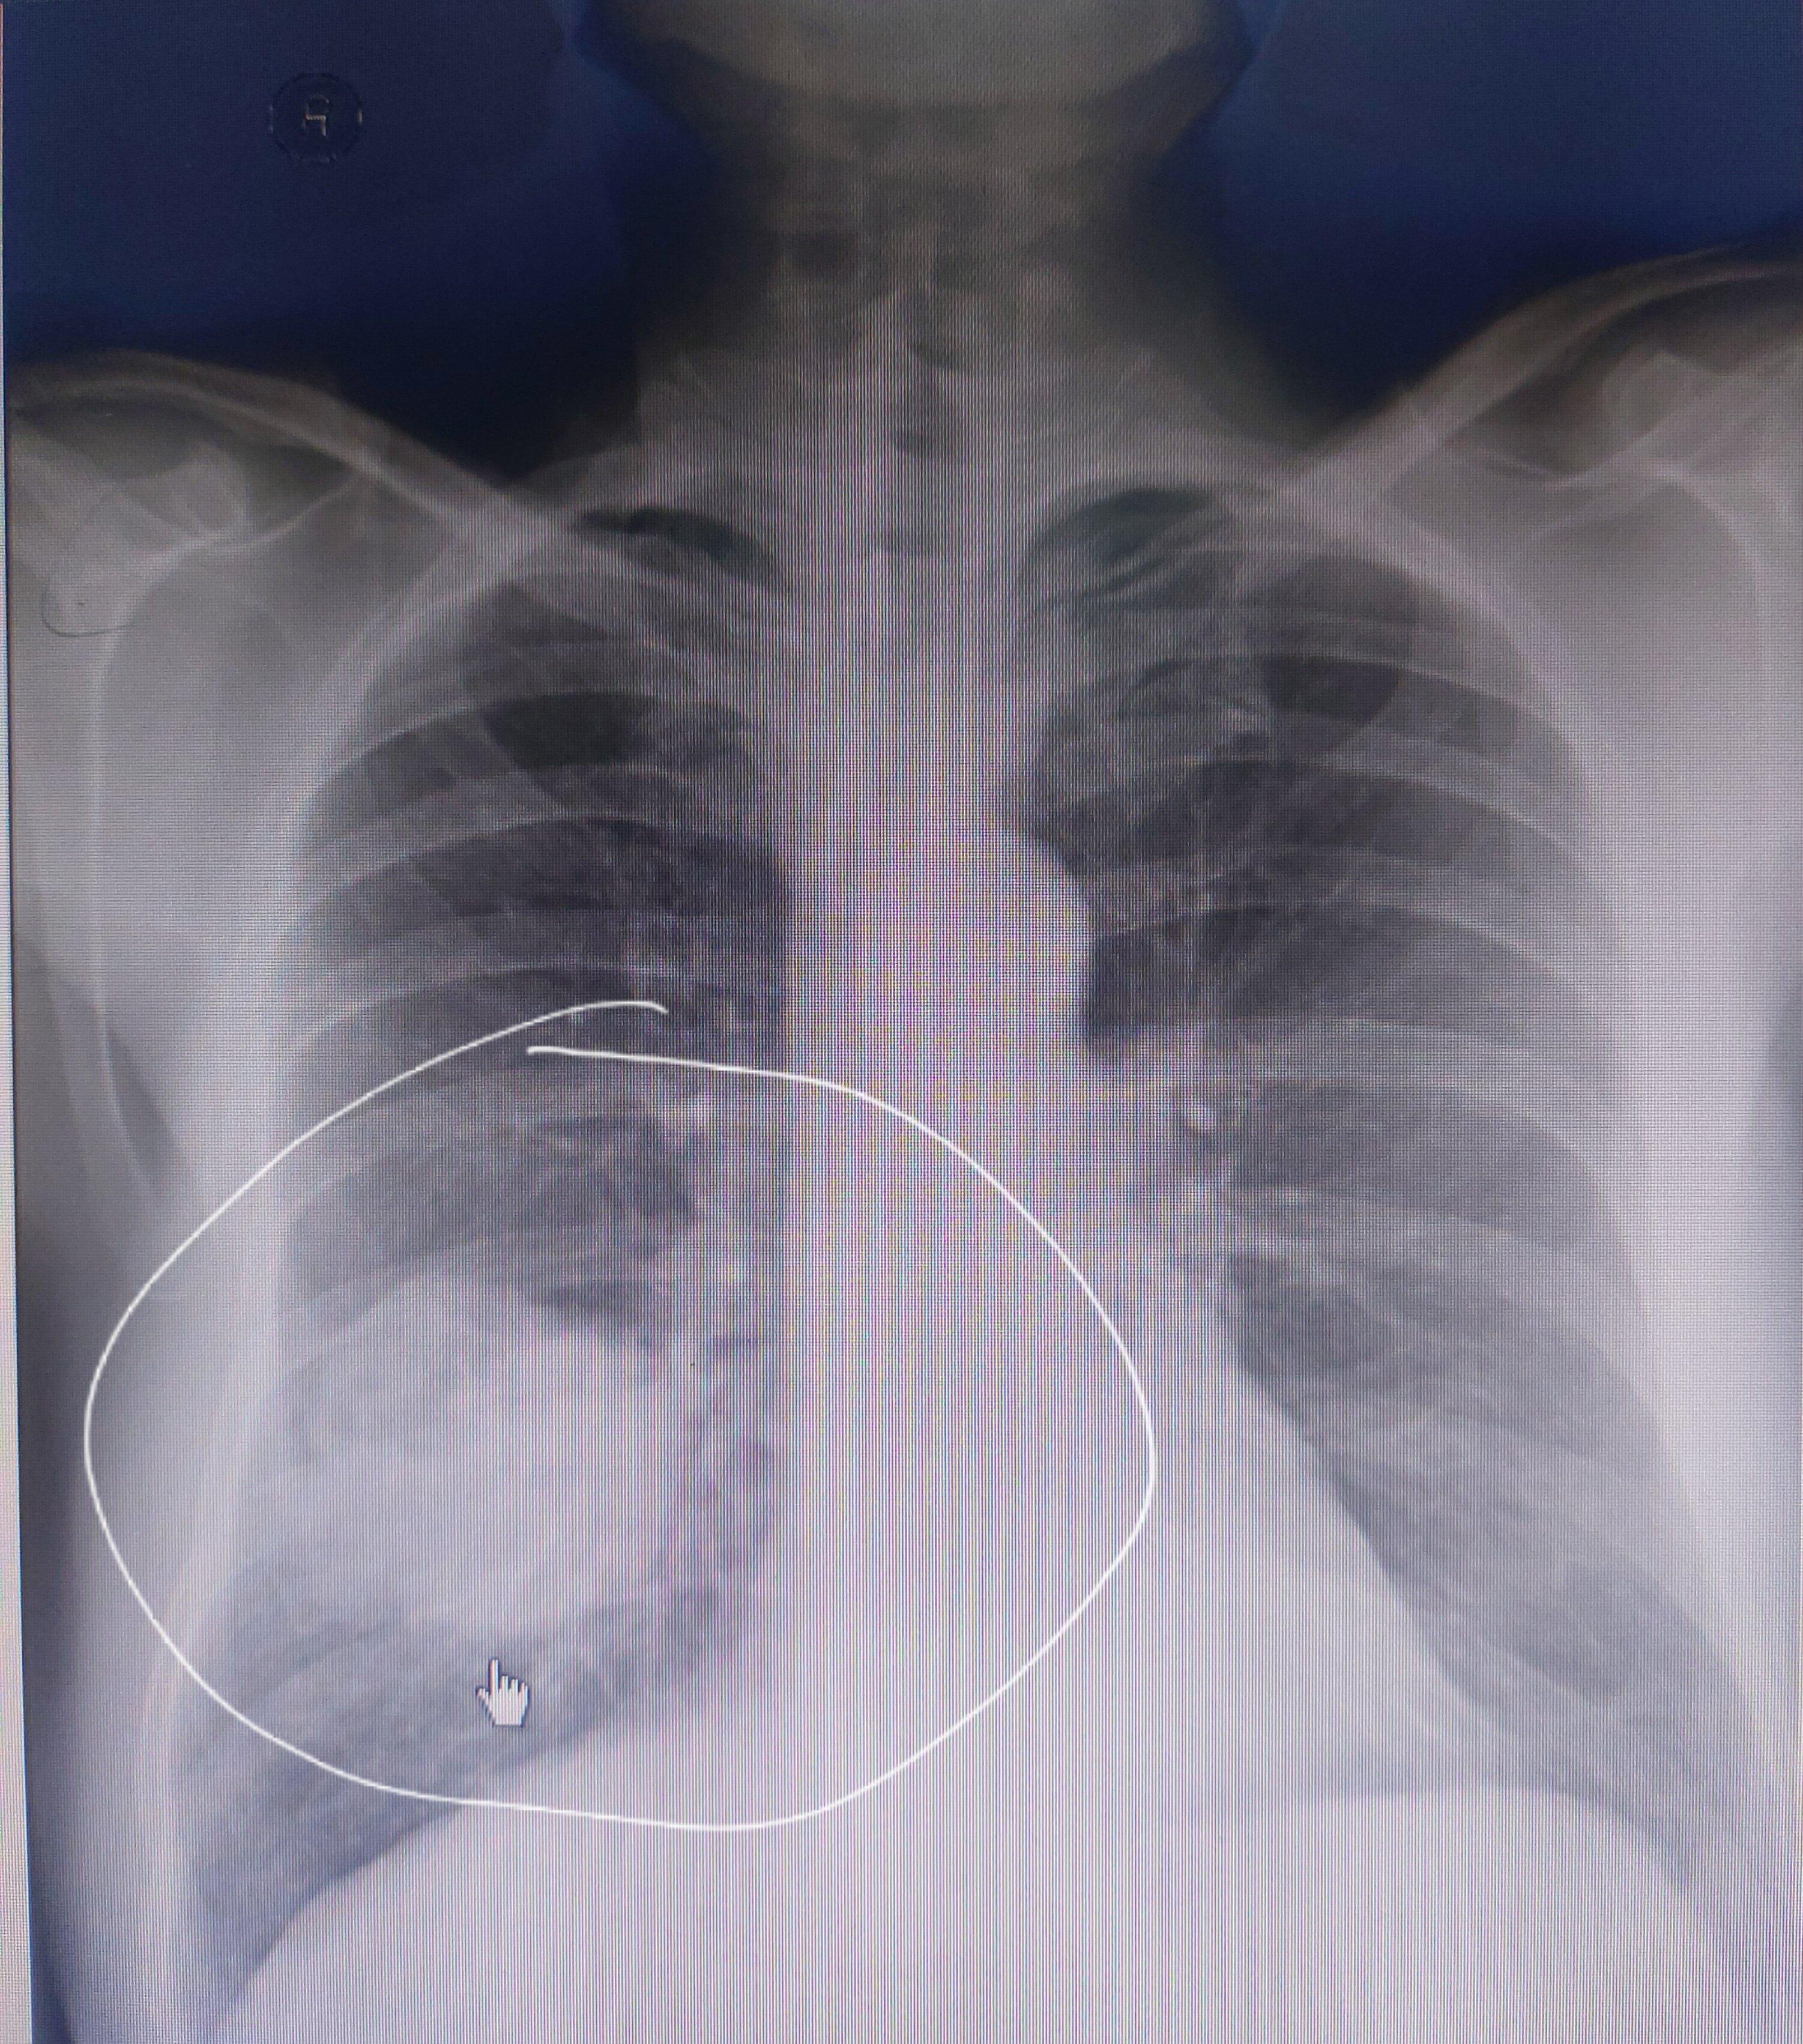

中央型肺癌的横s或者反s征,是指右侧中央型肺癌的正位x光胸片上的典型

图片尺寸1123x1280